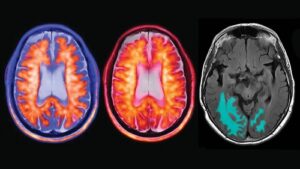

Las imágenes PET y MRI de amiloide muestran a un paciente con enfermedad de Alzheimer temprana. (Dr. Suzie Bash)

Lo que comenzó como una corrección motora se transformó en un hallazgo accidental que cuestiona el dogma de que la enfermedad de alzhéimer es incurable. Tras someterla a un procedimiento de ultrasonido focalizado de alta intensidad (FUS), la cognición de su madre se ‘encendió’ inesperadamente: recuperó la capacidad de reconocer a sus familiares, expresó necesidades emocionales y logró realizar cálculos, como contar hacia atrás desde 100 de siete en siete. Este resultado anecdótico ha llevado a Sun a iniciar un ensayo clínico con siete pacientes, donde dos ya han mostrado una «rápida mejoría» y el resto presenta una tasa media de recuperación del 50 por ciento.